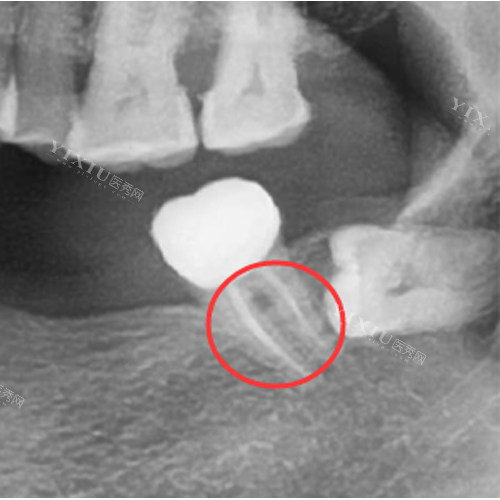

影像学检查:需拍摄不同角度的X线片,必要时结合CBCT评估堵塞位置和程度

探查测试:使用不同型号的根管锉探查,确定堵塞物的性质和可疏通性